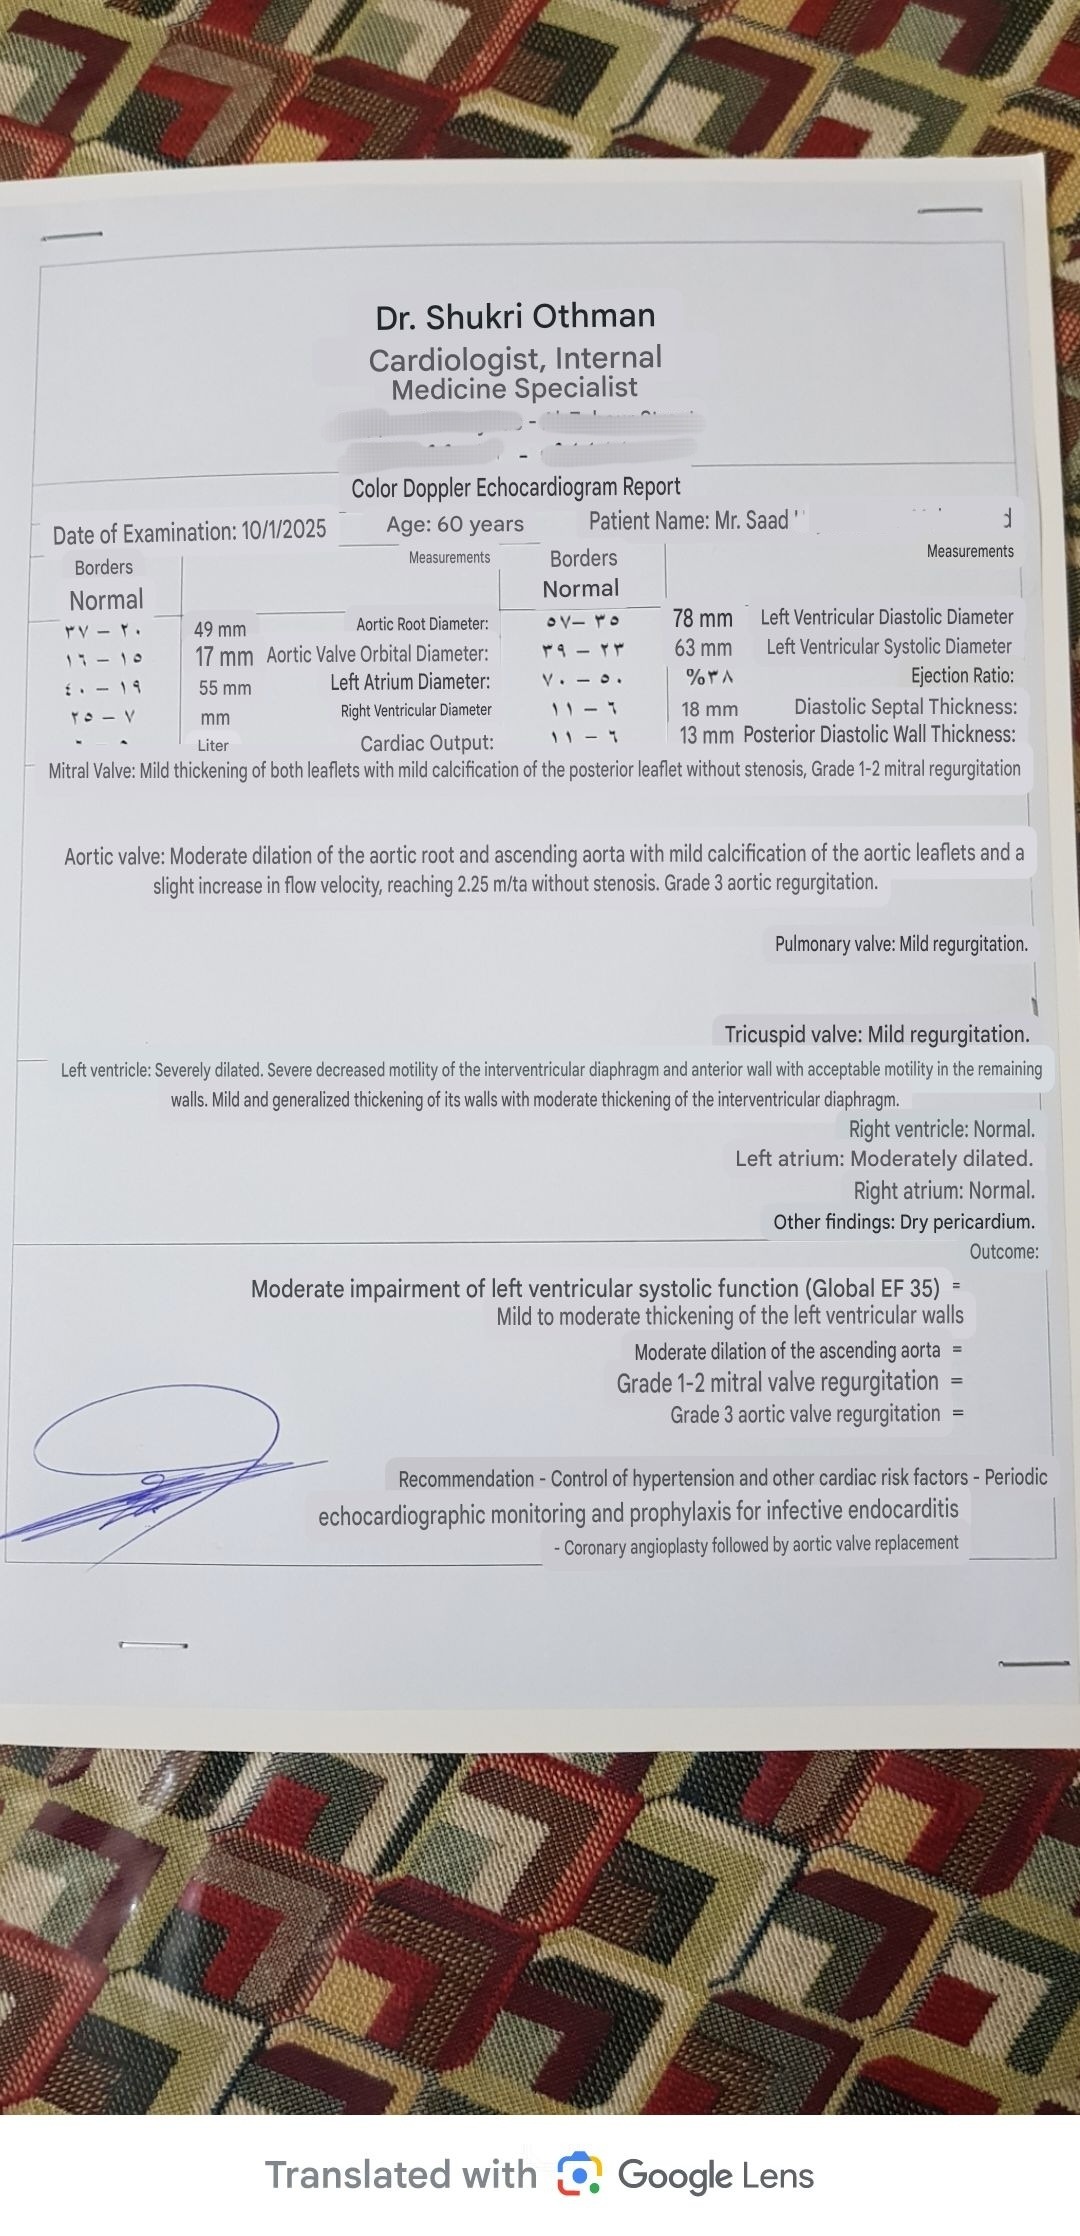

Second image : The Doppler echocardiogram scan .